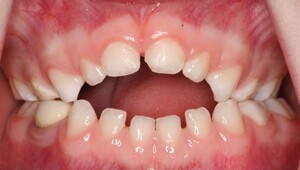

While both digit sucking and pacifier use cause effects on the developing dentition, pacifier use has been found to have a more detrimental effect on the occlusion.11 In addition, there is some evidence that prolonged use of pacifiers can contribute to speech difficulties. However, the evidence base for this is limited.12 If pacifier use continues beyond the age of three, there is a higher reported incidence of anterior open bite (Figure 1) and posterior crossbite compared to digit sucking, with the extent of these changes proportional to the longevity of the habit. Orthodontic pacifiers (Figure 2) may cause less detrimental effects on the occlusion than conventional ones; however, the evidence for this is limited.13 During prolonged thumb-sucking, the tongue is depressed, causing a change in the balance of forces between the tongue and the cheeks. In addition, the negative pressure caused by the sucking action can cause constriction of the upper arch, leading to the development of transverse discrepancies, manifesting in posterior crossbites.14 Prolonged digit pressure also leads to intrusion and proclination of the upper incisors and retroclination of the lower incisors, creating the features characteristic of an Angle’s Class II Division 1 malocclusion (Figure 3). Studies have shown that digit sucking is more likely to cause an increased overjet than pacifier use.3 An overjet greater than 6mm, alongside a loss of lip competency, has been shown to more than double the risk of trauma to the dentition.2 The positioning of the digit causes separation and subsequent overeruption of the teeth posteriorly, leading to an anterior open bite, which is often characteristically asymmetrical, depending on the digit(s) being sucked.